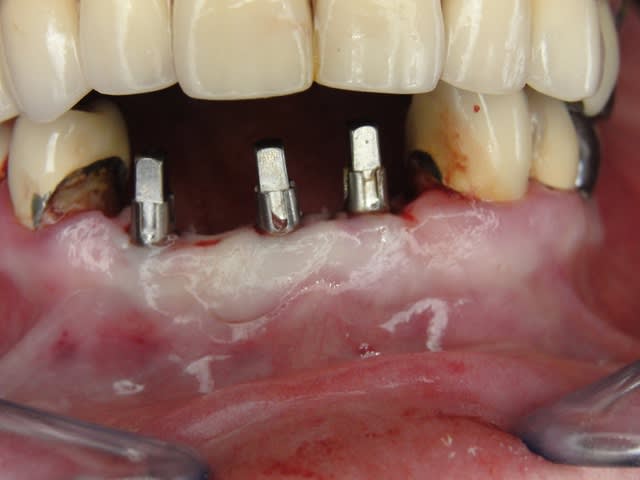

A défaut d'une chir en direct .. voilà une petite histoire en photos ou comment en 90 minutes passer d'un partiel résine à ...7 implants sur provisoires..stabilité primaire 60N grace à la technique MIMI ( oui.. post spécial ce Week end)..:)

Il n'y a jamais de questions stupides. Merci à ceux qui s'interrogent ..donc les hauteurs de s'interrogent caps existent mais pour gérer l'enfoncement de l'implant et pour aussi proposer des différentes hauteur de pilier : autrement formulé en fonction de la position de la rainure de la gérer carrée on a deux millimètres de marge/niveau gingival selon le choix du prep cap. Cela permet de placer le prep cap lorsque l'implant a du être enfoncé plus profondément ou bien si la hauteur de gencive est plus importante que les deux millimètres classiques de l'espace biologique usuel. (description sur le site du fabricant...shop online entre autre.)

Exp dans ce cas 4,5/10mm en 36 dans un site d'extraction récent placé en 12mm soit deux millimètres plus profondément j'ai scellé un prep cap angulé 5 degrés niveau 1/0 dont la limite s'arrête à la rainure de la tête carrée, pour 37 3,5/10mm placé en 10mm j'ai utilisé un prep cap 2/2mm. On prend vite l'habitude moi j'utilise que 2 modèles en zircone et 3 en titane..

Avec la chir trans gingivale technique MIMI ( Oui..un post sur la technique bientôt ..) j'ai pu placer deux 3,5/8mm..aurai je eu le meme résultat avec un lambeau..j'en doute..Les couronnes sont en titane. Recul clinique 2 ans ras. Simple efficace rapide moins onéreux satisfaisant pour le praticien et la patiente..

Maintenant concernant la demande de scans : je poste ce cas, une patiente vient me voir avec son scan car elle a consulté d'autres "spécialistes" et on lui refuse la pose d'implant secteur 4 où alors avec greffe préalable..Ca se discute..pas de temps à perdre je sais faire autrement..